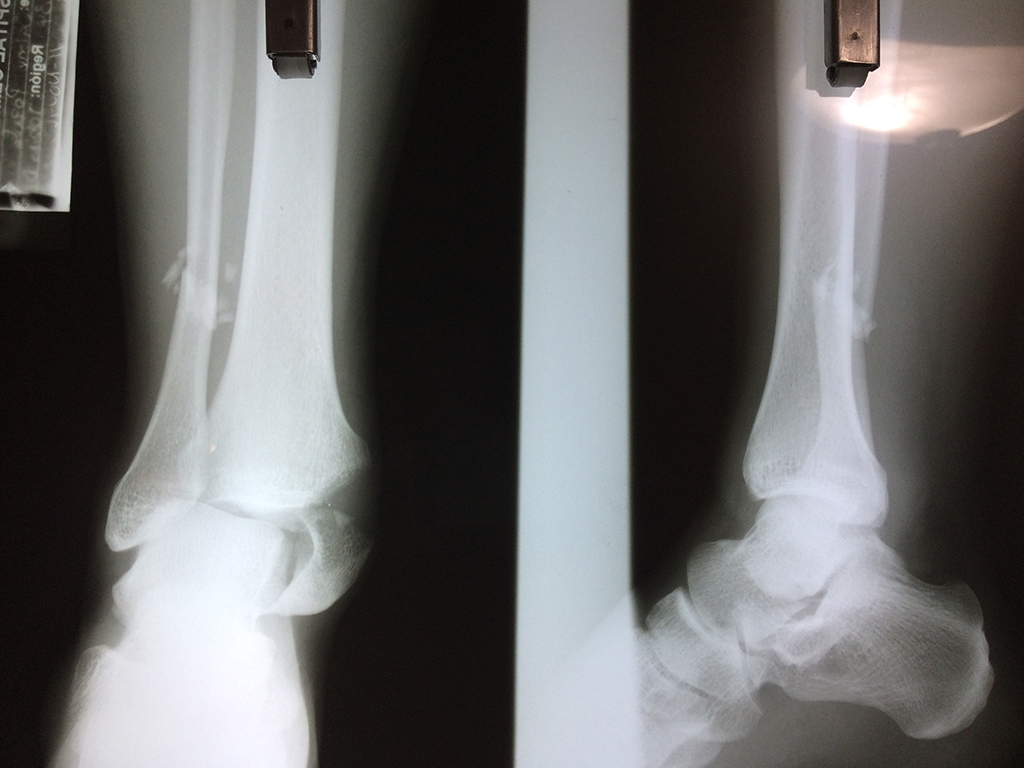

Una fractura de tobillo es la rotura de uno o más de los huesos del tobillo. Estas fracturas pueden ser:

Algunas fracturas de tobillo pueden requerir cirugía si:

- Los extremos de los huesos están desalineados entre sí (desplazados).

- La fractura se extiende hasta la articulación del tobillo (fractura intra-articular).

Cuando se necesita cirugía, es probable que esta implique el uso de clavijas de metal, tornillos o placas para sostener los huesos en su lugar mientras la fractura se consolida. Los elementos de soporte pueden ser temporales o permanentes.